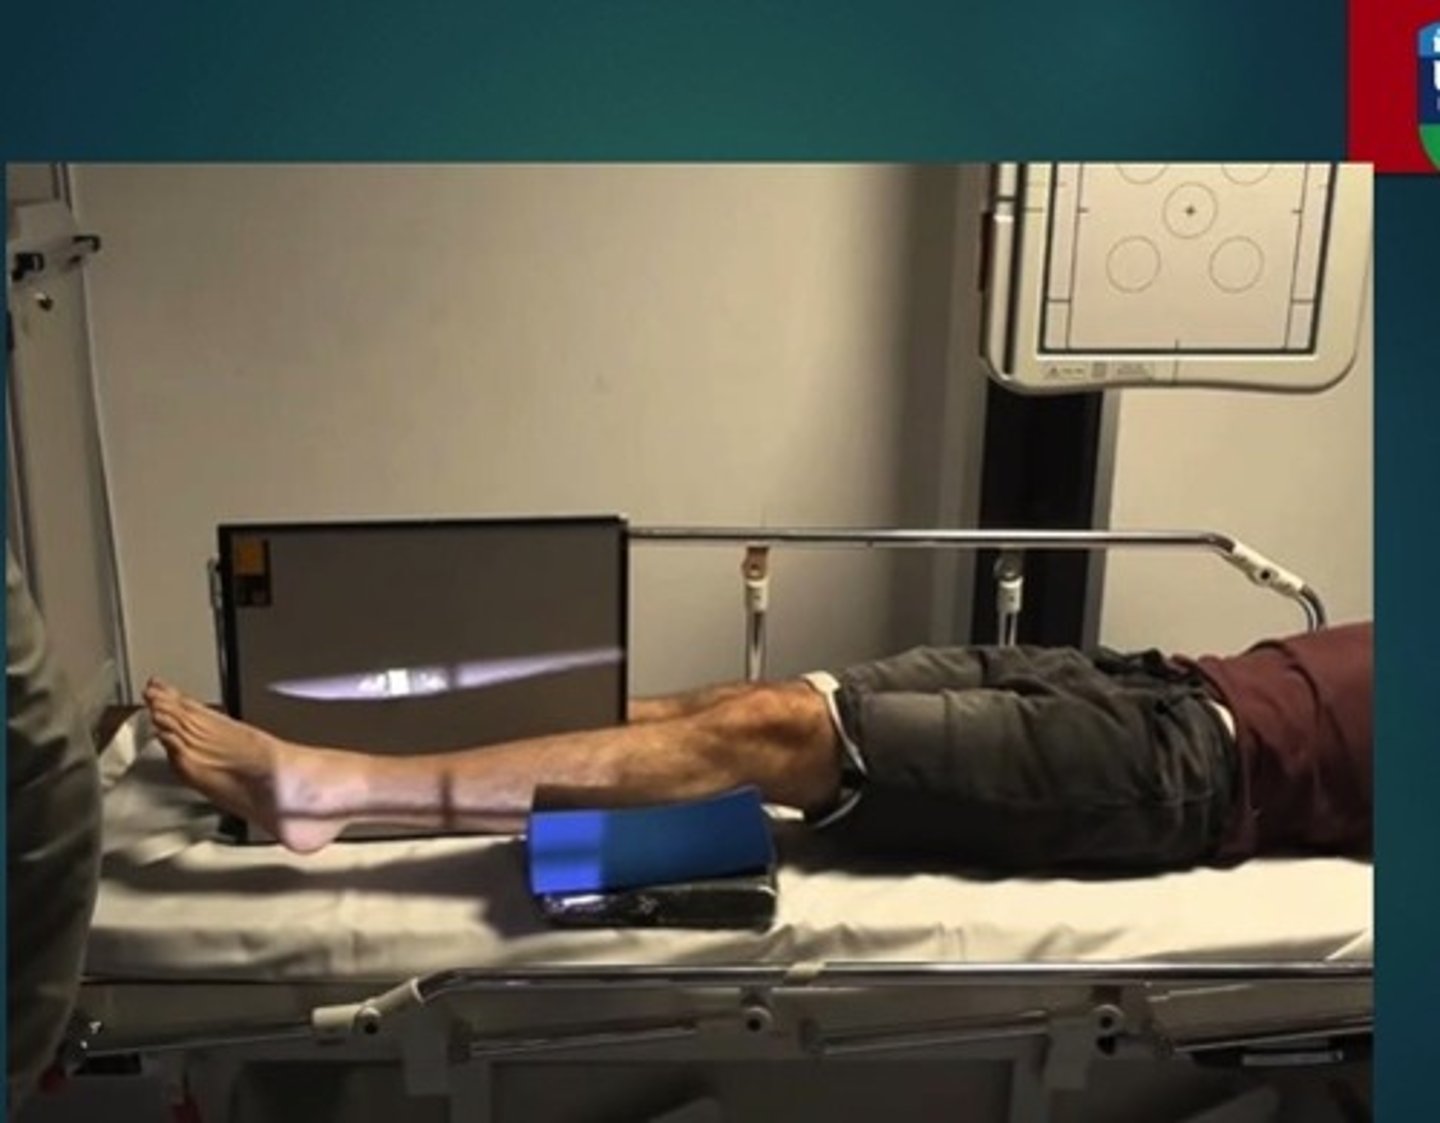

Describe, in detail, the positioning of the PATIENT for a LATERAL TIBIA & FIBULA projection.

1. From the AP position, the patient turns onto the affected side. Lateral aspect of the leg in contact with the IR.

2. The knee joint is flexed.

3. The malleoli should be superimposed (in practice the toes are slightly elevated). The condyles of the knee should also be superimposed.

4. The foot is dorsi-flexed (bringing the plantar aspect 90° to the image detector).

5. The long axis of the tibia should be parallel to the image detector.

How should we position the X-RAY TUBE for a LATERAL projection of the TIBIA & FIBULA?

SID

Central ray

Centring point

SID: 100 - 115cm

Central ray: perpendicular to the IR

Centring point: in the midline; midway between the knee and ankle joint

How should we COLLIMATE when doing a LATERAL projection of the TIBIA & FIBULA?

- to include the entire length of the tibia and fibula bones and lateral soft tissue borders. The knee and ankle joint must also be included.